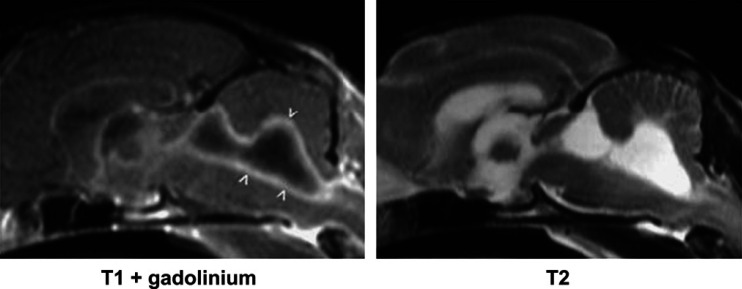

Fig 1.

Example of lesions that are visible only in T1-weighted images obtained after gadolinium contrast medium administration. Relatively uniform, diffuse enhancement is evident affecting the meninges (arrowheads) of this cat with FIP. The T1- and T2-weighted images appear normal.